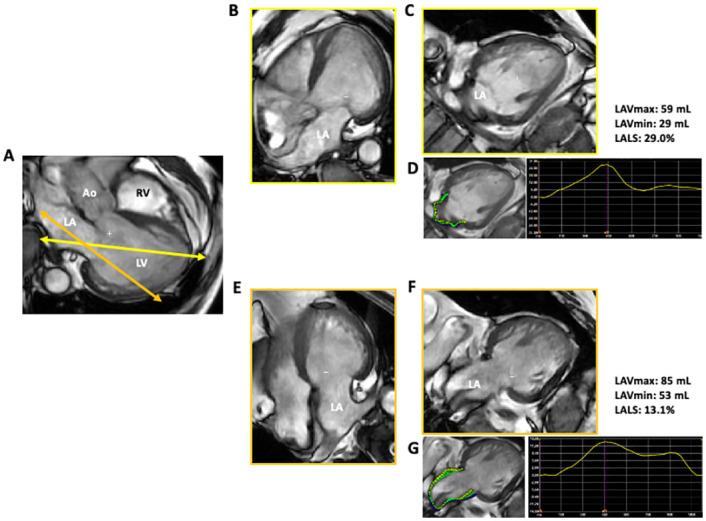

In this study, 4 types of cohorts were included: 1. 105 normal subjects (retrospectively), 2. 53 patients with cardiovascular diseases (retrospectively), 3. 15 patients who received cardiac magnetic resonance (prospectively), and 4. 20 normal subjects (prospectively). LALS and LA length were measured using both 2DE and 3DE in 105 healthy subjects (median age: 42 years). Biplane LALS was measured in apical four- and two-chamber views using 2DE speckle tracking software, and 3DE LALS was measured using new 3DE LA strain software. To determine sensitivity, we also performed the same analysis in 53 patients with cardiovascular disease. The mean value of biplane LALS was 39.6%. LA length at both end-diastole (r = -0.43) and end-systole (r = -0.54) was negatively correlated with biplane LALS. Multivariate regression analysis revealed that both end-diastolic and end-systolic LA length had significant negative relationships with biplane LALS after adjusting for anthropometric and echocardiographic image quality parameters. 3DE LALS (23.7±7.6%) gave significantly lower values than 2DE LALS (39.5±12.0%, p<0.001) with a weak correlation (r = 0.33). LA length measured by 2DE was significantly shorter than that measured by 3DE. The same trend was observed in diseased patients.

Our results revealed that in 2DE, the LA cavity consistently appears longitudinally foreshortened in apical views, potentially overestimating LALS. 3DE may overcome this limitation.

本研究纳入了 4 种队列:1. 105 名正常受试者(回顾性);2. 53 名心血管疾病患者(回顾性);3. 15 名接受心脏磁共振检查的患者(前瞻性);4. 20 名正常受试者(前瞻性)。在 105 名健康受试者(中位年龄:42 岁)中,使用 2DE 和 3DE 分别测量 LALS 和左心房长度。使用 2DE 斑点追踪软件在心尖四腔心和两腔心切面测量双平面 LALS,使用新的 3DE LA 应变软件测量 3DE LALS。为了确定敏感性,我们还对 53 名心血管疾病患者进行了相同的分析。双平面 LALS 的平均值为 39.6%。舒张末期(r = -0.43)和收缩末期(r = -0.54)的左心房长度与双平面 LALS 呈负相关。多变量回归分析显示,在调整了人体测量和超声心动图图像质量参数后,舒张末期和收缩末期左心房长度与双平面 LALS 均呈显著负相关。3DE LALS(23.7±7.6%)明显低于 2DE LALS(39.5±12.0%,p<0.001),两者相关性较弱(r = 0.33)。2DE 测量的左心房长度明显短于 3DE 测量的长度。在患病患者中也观察到了相同的趋势。

我们的结果表明,在 2DE 中,心尖切面始终显示 LA 腔呈纵向缩短,可能高估 LALS。3DE 可能克服这一局限性。